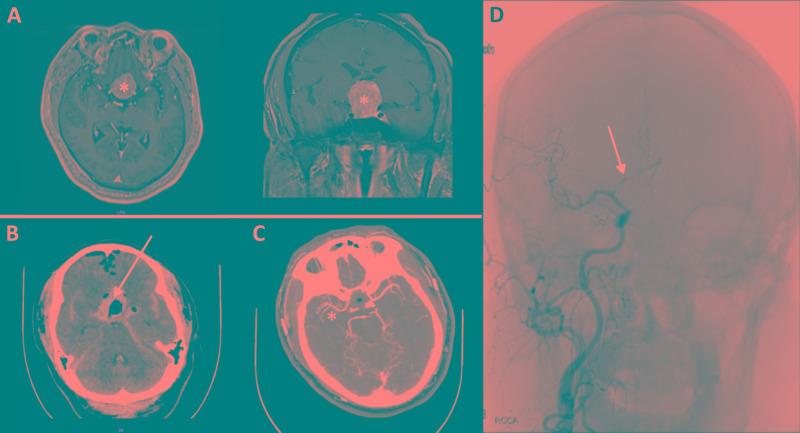

Cerebral vasospasm is a rare life-threatening complication of transsphenoidal surgery (TSS). We report our experience with two cases of symptomatic vasospasm after endoscopic TSS, alongside a systematic review of published cases. Two patients who underwent endoscopic TSS for resection of a tuberculum sella meningioma (case 1) and pituitary adenoma (case 2) developed symptomatic vasospasm. Clinical variables, including demographics, histopathology, the extent of subarachnoid hemorrhage (SAH), diabetes insipidus (DI), day of vasospasm, vasospasm symptoms, vessels involved, management, and clinical outcome, were retrospectively extracted. We subsequently reviewed published cases of symptomatic post-TSS vasospasm. Including our two cases, we identified 34 reported cases of TSS complicated by symptomatic vasospasm. Female patients accounted for 20 (58.8%) of 34 cases. The average age was 48.1 ± 12.9 years. The majority of patients exhibited postoperative SAH (70.6%). The average delay to vasospasm presentation was 8.5 ± 3.6 days. The majority of patients exhibited vasospasm in multiple vessels, typically involving the anterior circulation. Hemodynamic augmentation with hemodilution, hypertension, and hypervolemia was the most common treatment. Death occurred in six (17.6%) of 34 patients. Common deficits included residual extremity weakness (17.6%), pituitary insufficiency (8.8%), and cognitive deficits (8.8%). Symptomatic vasospasm is a rare, potentially fatal complication of TSS. The most consistent risk factor is SAH. Early diagnosis requires a high index of suspicion when confronted with intractable DI, acute mental status change, or focal deficits in the days after TSS. Morbidity and death are significant risks in patients with this complication.

脑血管痉挛是经蝶窦手术(TSS)罕见的危及生命的并发症。我们报告了两例内镜下TSS术后出现症状性血管痉挛的经验,并对已发表病例进行了系统回顾。两名因切除鞍结节脑膜瘤(病例1)和垂体腺瘤(病例2)而接受内镜下TSS的患者出现了症状性血管痉挛。回顾性提取了临床变量,包括人口统计学、组织病理学、蛛网膜下腔出血(SAH)程度、尿崩症(DI)、血管痉挛发生日期、血管痉挛症状、受累血管、治疗方法及临床结局。随后,我们回顾了已发表的TSS术后症状性血管痉挛病例。包括我们的两例在内,我们共识别出34例报告的TSS合并症状性血管痉挛病例。34例患者中女性占20例(58.8%)。平均年龄为48.1±12.9岁。大多数患者术后出现SAH(70.6%)。血管痉挛出现的平均延迟时间为8.5±3.6天。大多数患者多支血管出现血管痉挛,通常累及前循环。血液稀释、高血压和高血容量的血流动力学强化是最常见的治疗方法。34例患者中有6例(17.6%)死亡。常见的后遗症包括肢体残留无力(17.6%)、垂体功能不全(8.8%)和认知缺陷(8.8%)。症状性血管痉挛是TSS罕见的、潜在致命的并发症。最一致的危险因素是SAH。TSS术后数天内,当面对难治性DI、急性精神状态改变或局灶性缺陷时,早期诊断需要高度的怀疑指数。这种并发症患者的发病率和死亡率风险很高。